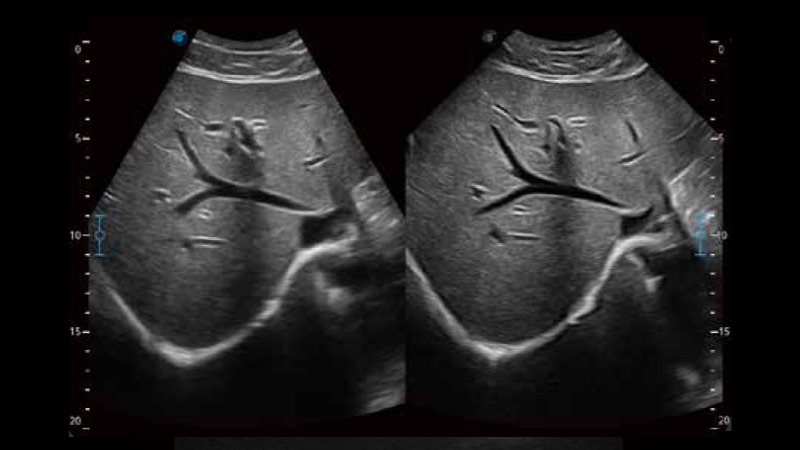

μ-Scan+新一代微米成像技术

新一代微米成像技术大大提高了器官和病变的可见性。高清对比度分辨率将抑制斑点噪声,同时保持真实的组织结构。